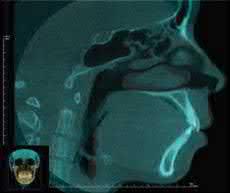

Cover Images: (top left) Image of human teeth courtesy of Joorok Park, (bottom left) line drawing of human gum courtesy of KJ Lee, (right) Scanned image of human skeleton courtesy of Dr. Tung Nguyen